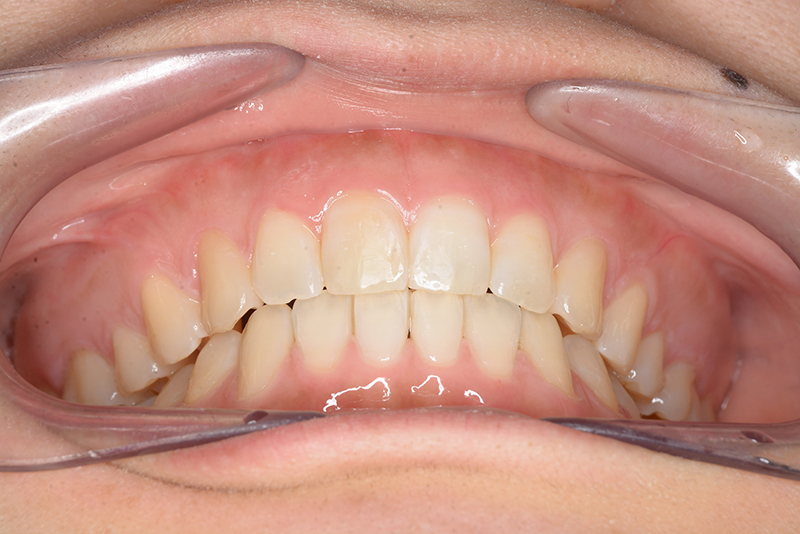

動的治療終了時

FP・IOP

批評・予后 上顎臼歯は軽度に近心傾斜しつつ、歯列遠心部には奥行きがあり、下顎歯列には叢生は認められず、スピー湾曲も軽度であること。また軟組織上の問題もないため、上顎歯列の遠心移動による治療が妥当だと判断した。治療後において上顎歯列の遠心傾斜と共に下顎はカウンタークロックワイズローテーションをしながら咬合の緊密化が得られた。